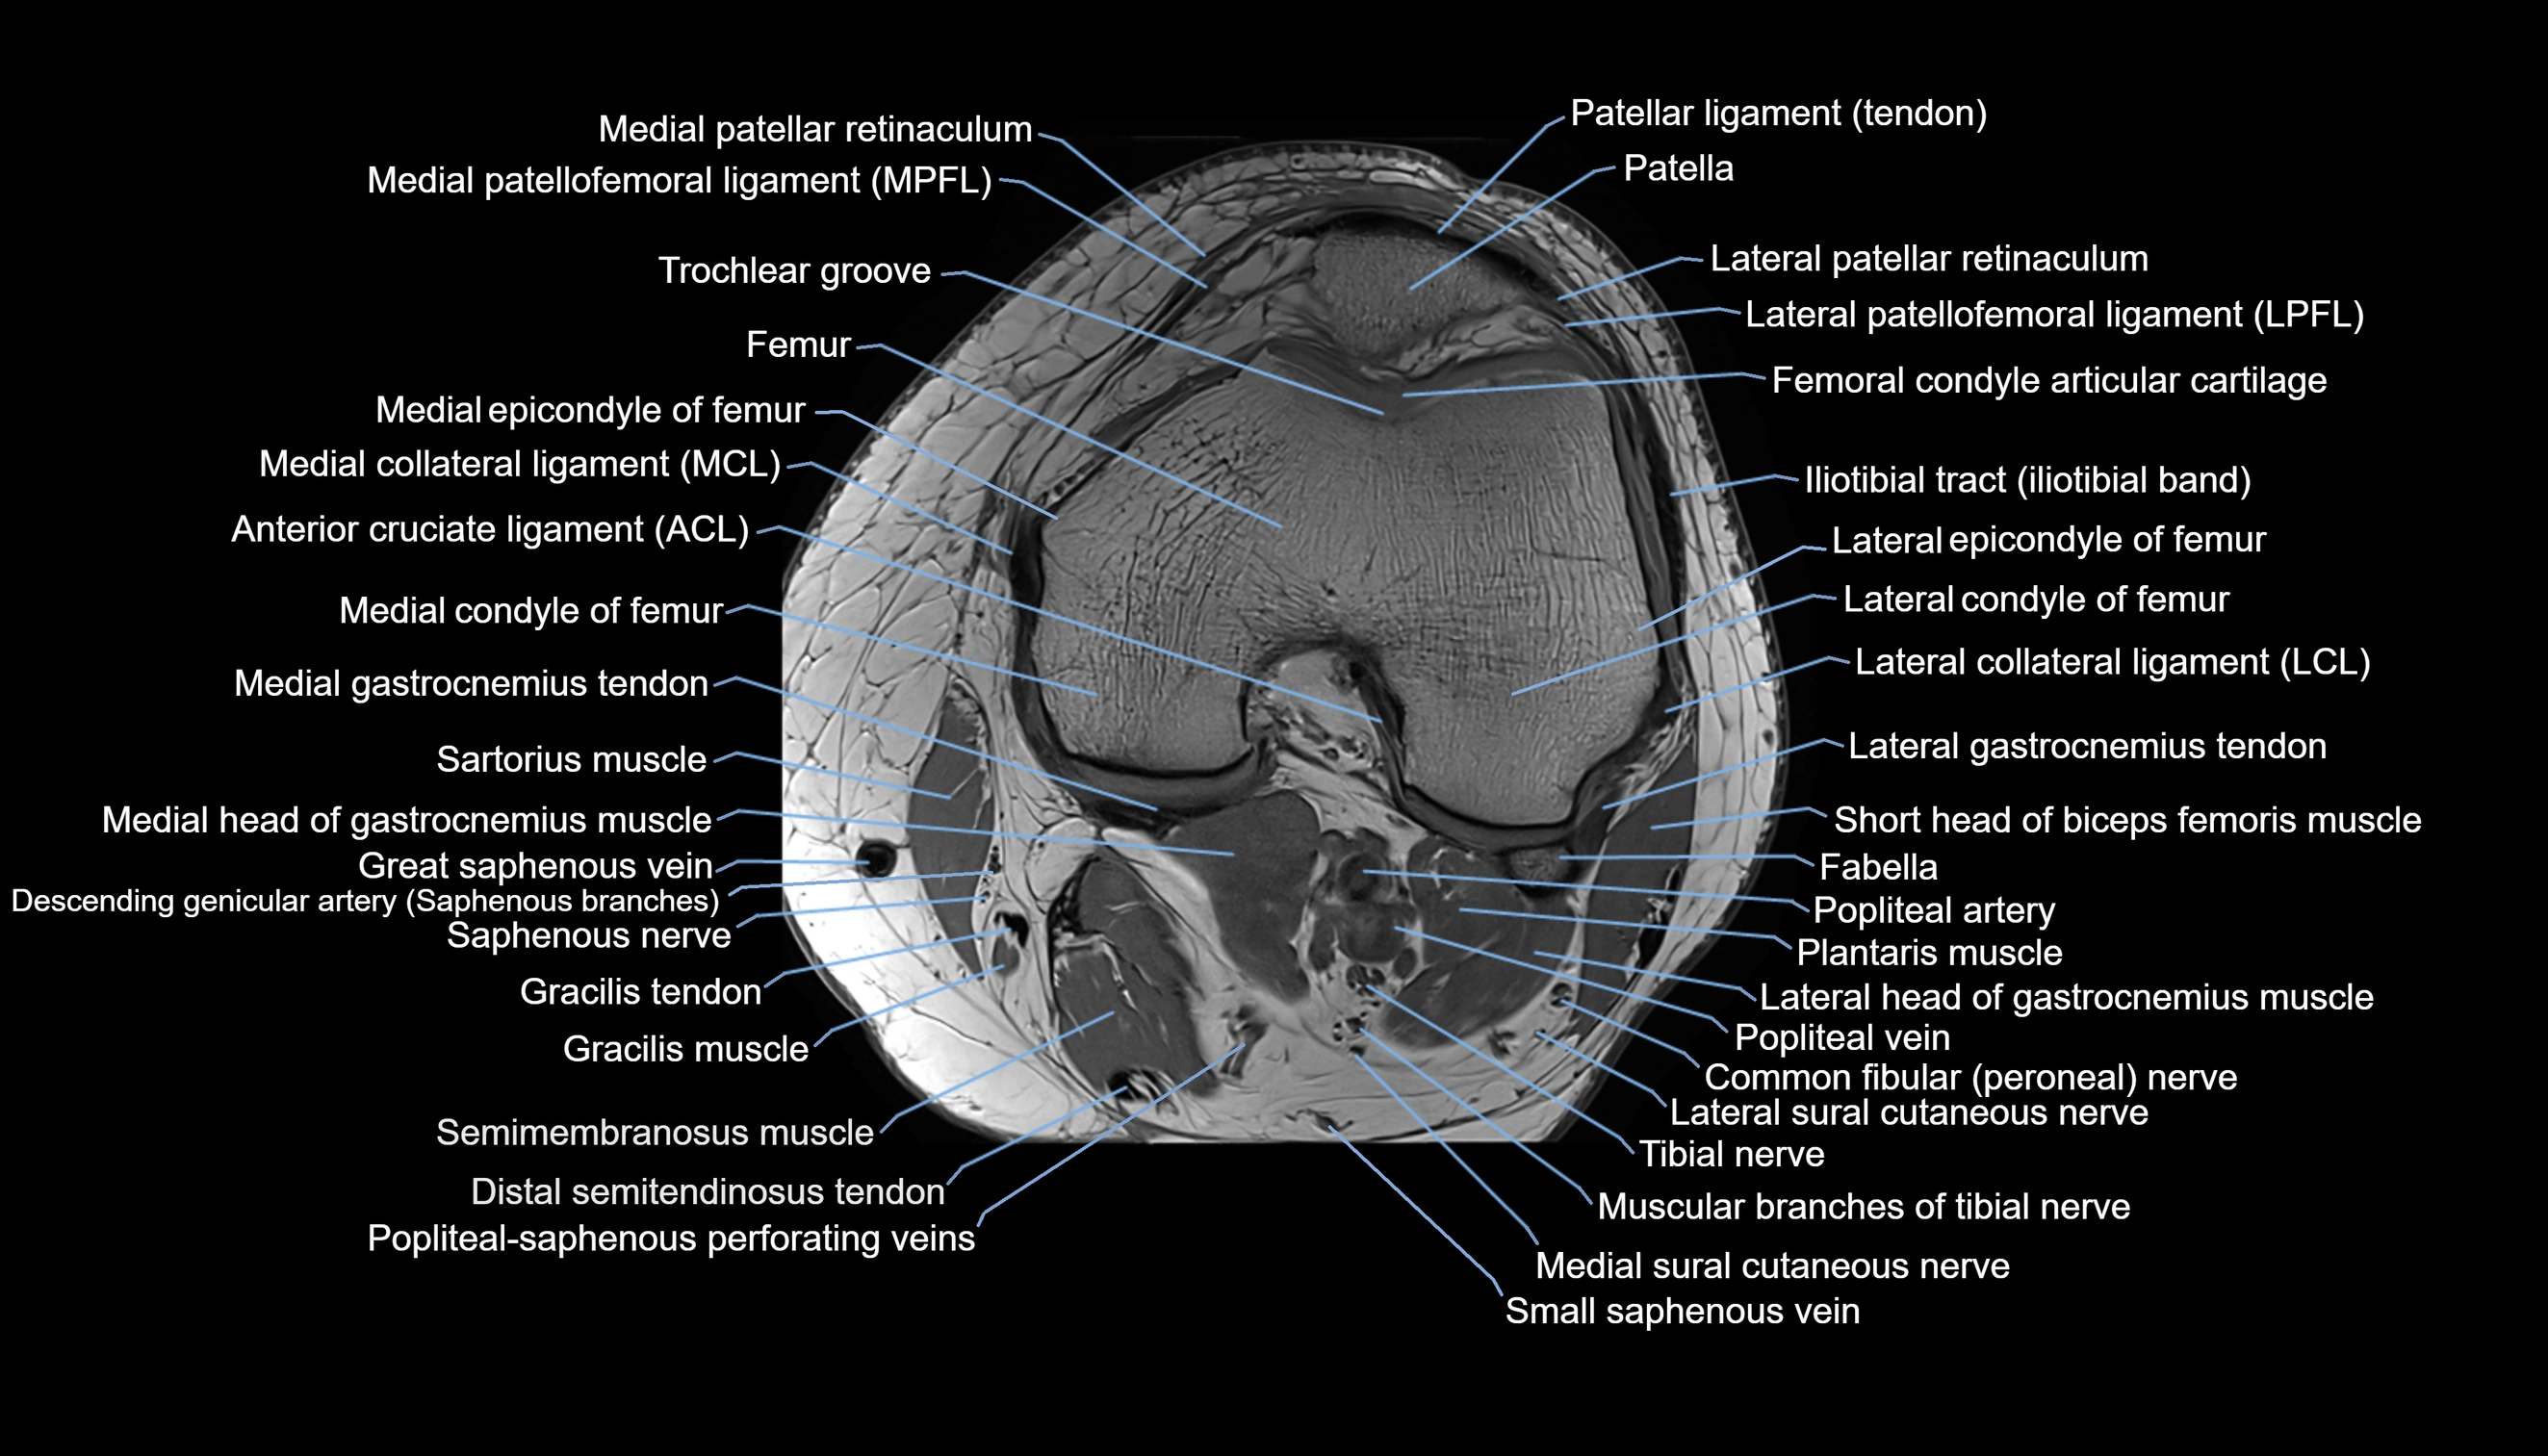

- Biceps femoris muscle (Short head)

- Descending genicular artery (Saphenous branch)

- Gracilis tendon (Distal)

- Lateral collateral ligament

- Lateral condyle of femur

- Lateral epicondyle of femur

- Lateral gastrocnemius tendon

- Lateral head of gastrocnemius muscle

- Lateral patellar retinaculum

- Lateral patellofemoral ligament

- Lateral sural cutaneous nerve

- Medial collateral ligament

- Medial condyle of femur

- Medial epicondyle of femur

- Medial gastrocnemius tendon

- Medial head of gastrocnemius muscle

- Medial patellar retinaculum

- Medial patellofemoral ligament

- Medial sural cutaneous nerve

- Muscular branches of tibial nerve

- Patella

- Patellar tendon (patellar ligament)

- Plantaris muscle

- Popliteal artery

- Popliteal vein

- Saphenous nerve

- Sartorius muscle

- Small saphenous vein

- Tibial nerve

- Trochlear groove